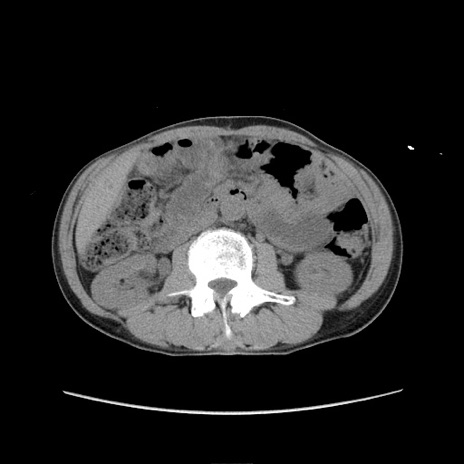

症例11(横断像)

【症例】 60歳代男性

【主訴】 下腹部痛

【現病歴】 本日夜中より下腹部痛の症状認め、受診。

【既往歴】 膀胱癌(膀胱全摘+尿管皮膚瘻術) 、胃癌術後

【身体所見】 BT 35.3℃、PR 58/min、BP 136/98mHg、腹部平坦、軟、腸蠕動音±、ストマ留置あり、左上腹部~正中部に圧痛あり、反跳痛なし。

【データ】WBC 5100、CRP0.01